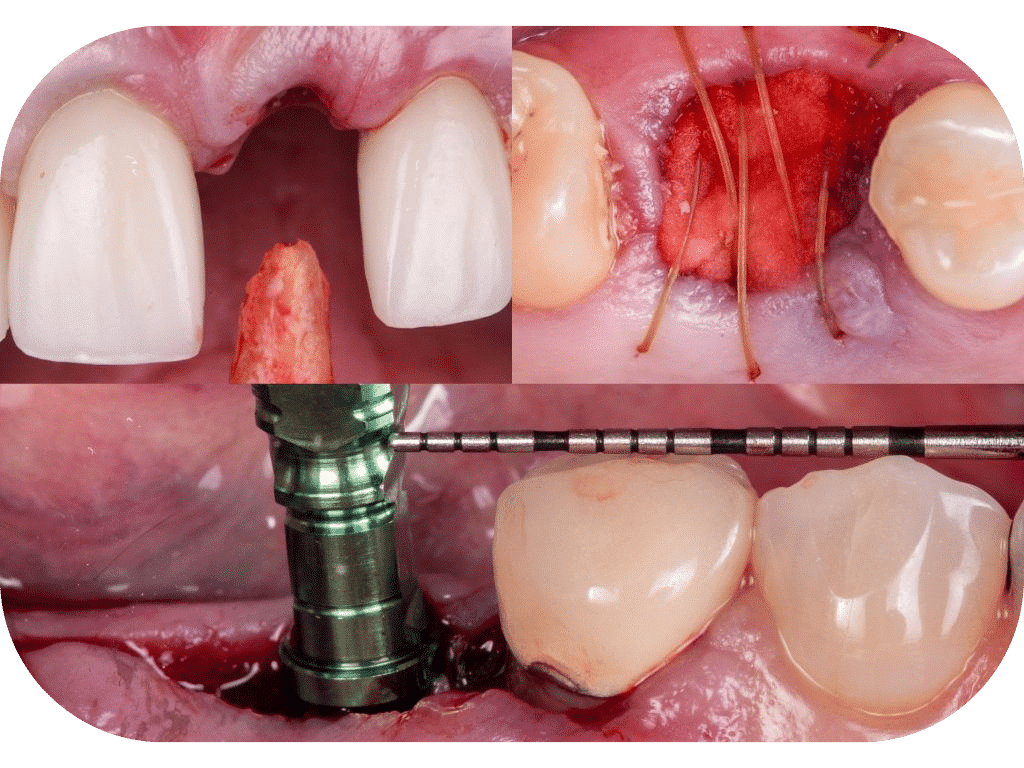

Hands-On Day 1: In this practical session, participants will master techniques for atraumatic extractions and socket grafting, learn efficient membrane placement for intact and damaged sockets, and refine suture techniques to ensure optimal patient outcomes.

Hands-On Day 2: This hands-on lab enables participants to design minor flaps effectively, perform single implant placement in different bone densities, and polish their suture techniques for secure wound closure..